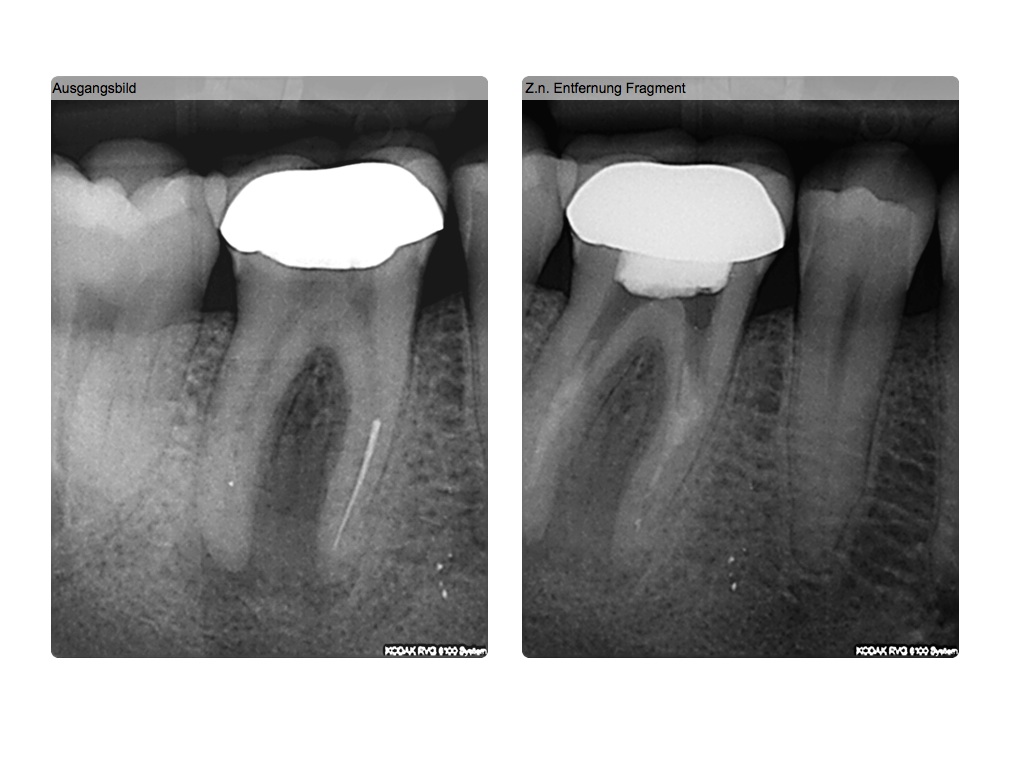

Röntgenbilder lügen…